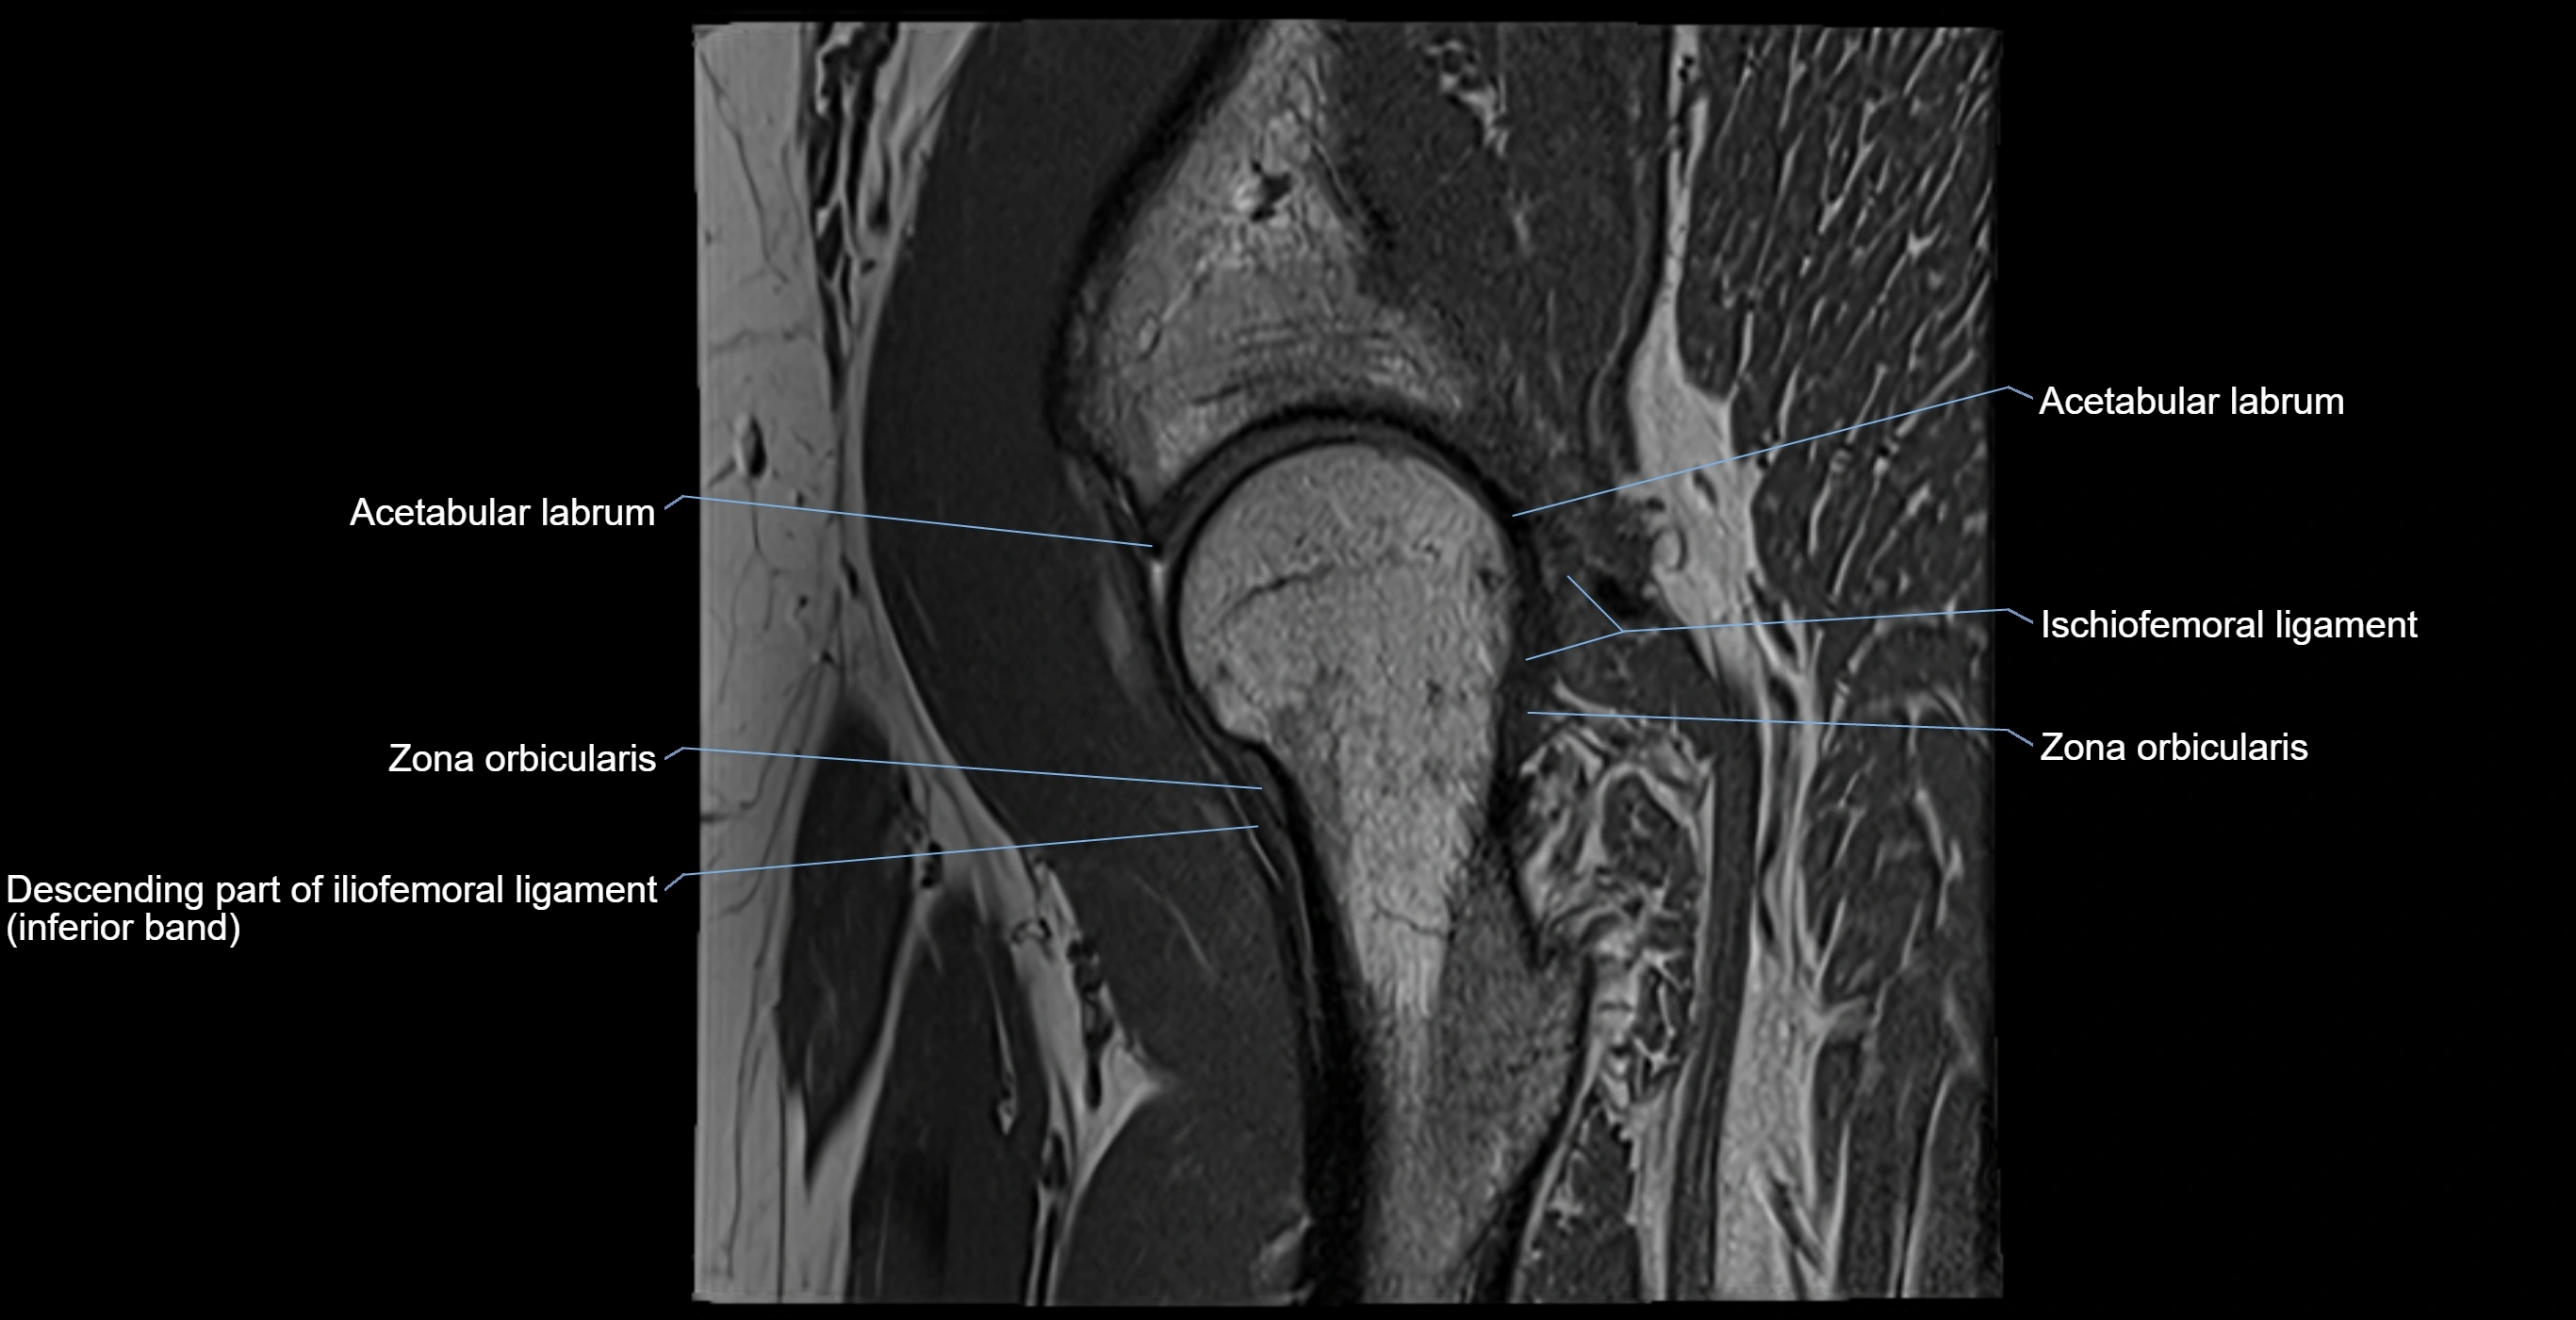

The acetabular labrum is a fibrocartilaginous ring that surrounds the rim of the acetabulum in the hip joint. It deepens the hip socket, increases joint stability, and maintains a suction seal that preserves negative intra-articular pressure. Structurally, the labrum transitions from hyaline cartilage of the acetabulum to dense fibrocartilage at its free edge.

It is triangular in cross-section, with its base attached to the acetabular rim and its apex projecting toward the femoral head. The labrum is most robust superiorly and anteriorly, where load bearing is greatest, and relatively thinner inferiorly.

Structure and Relations

• Superior and anterior labrum: thickest portions, stabilizing against anterior dislocation

• Inferior labrum: blends with the transverse acetabular ligament bridging the acetabular notch

MRI Appearance

T1-weighted images:

• Labrum: low signal intensity (dark)

• Surrounded by intermediate signal joint fluid (bright on arthrogram)

• Tears: linear or focal areas of intermediate-to-high signal interrupting labral continuity

T2-weighted images:

• Joint fluid: bright, making labral tears visible as fluid extending into or around labrum

• Degeneration: may show areas of increased signal within labrum